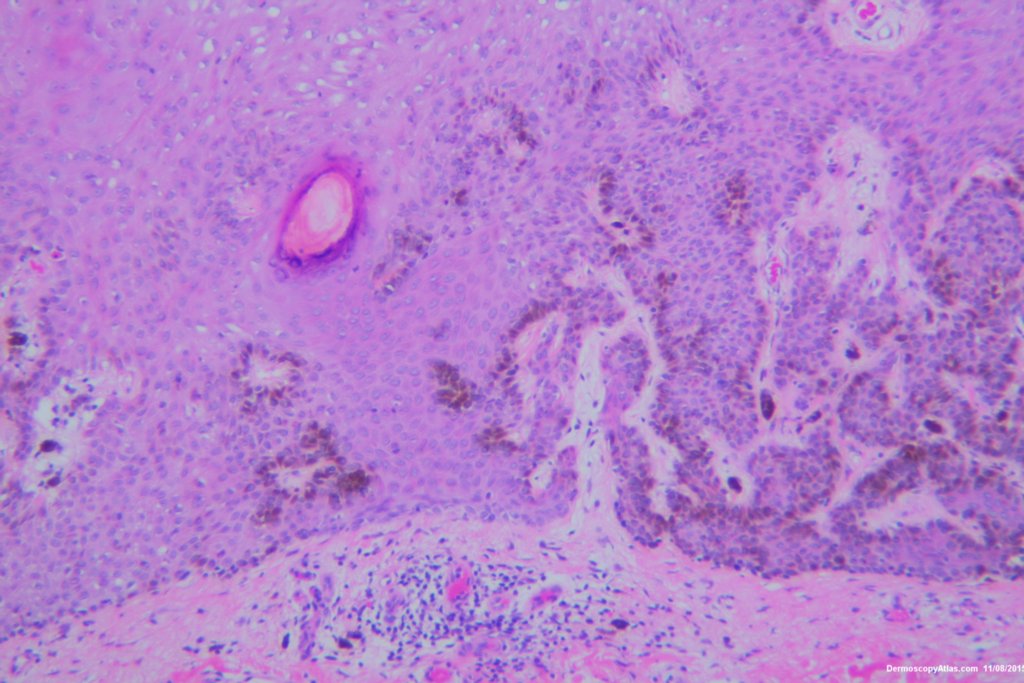

Image Number #3374 (Seborrhoeic keratosis irritated)

Diagnosis: Seborrhoeic keratosis irritated

Description: Pigmented lesion back

This lesion looked darker than the many other seborrhoeic keratoses on this elderly man's back. It was thought there might be a lentiginous proliferation of atypical melanocytes in the lesion . Also the multiple colours and the white lines were unusual for a seborrhoeic keratosis. However pathology of a large shave biopsy excision showed only a pigmented thick seborrhoeic keratosis with increased pigment in normal basal keratinocytes. The blue colour was because of the depth of the lesion ie thick. No idea why the white lines!